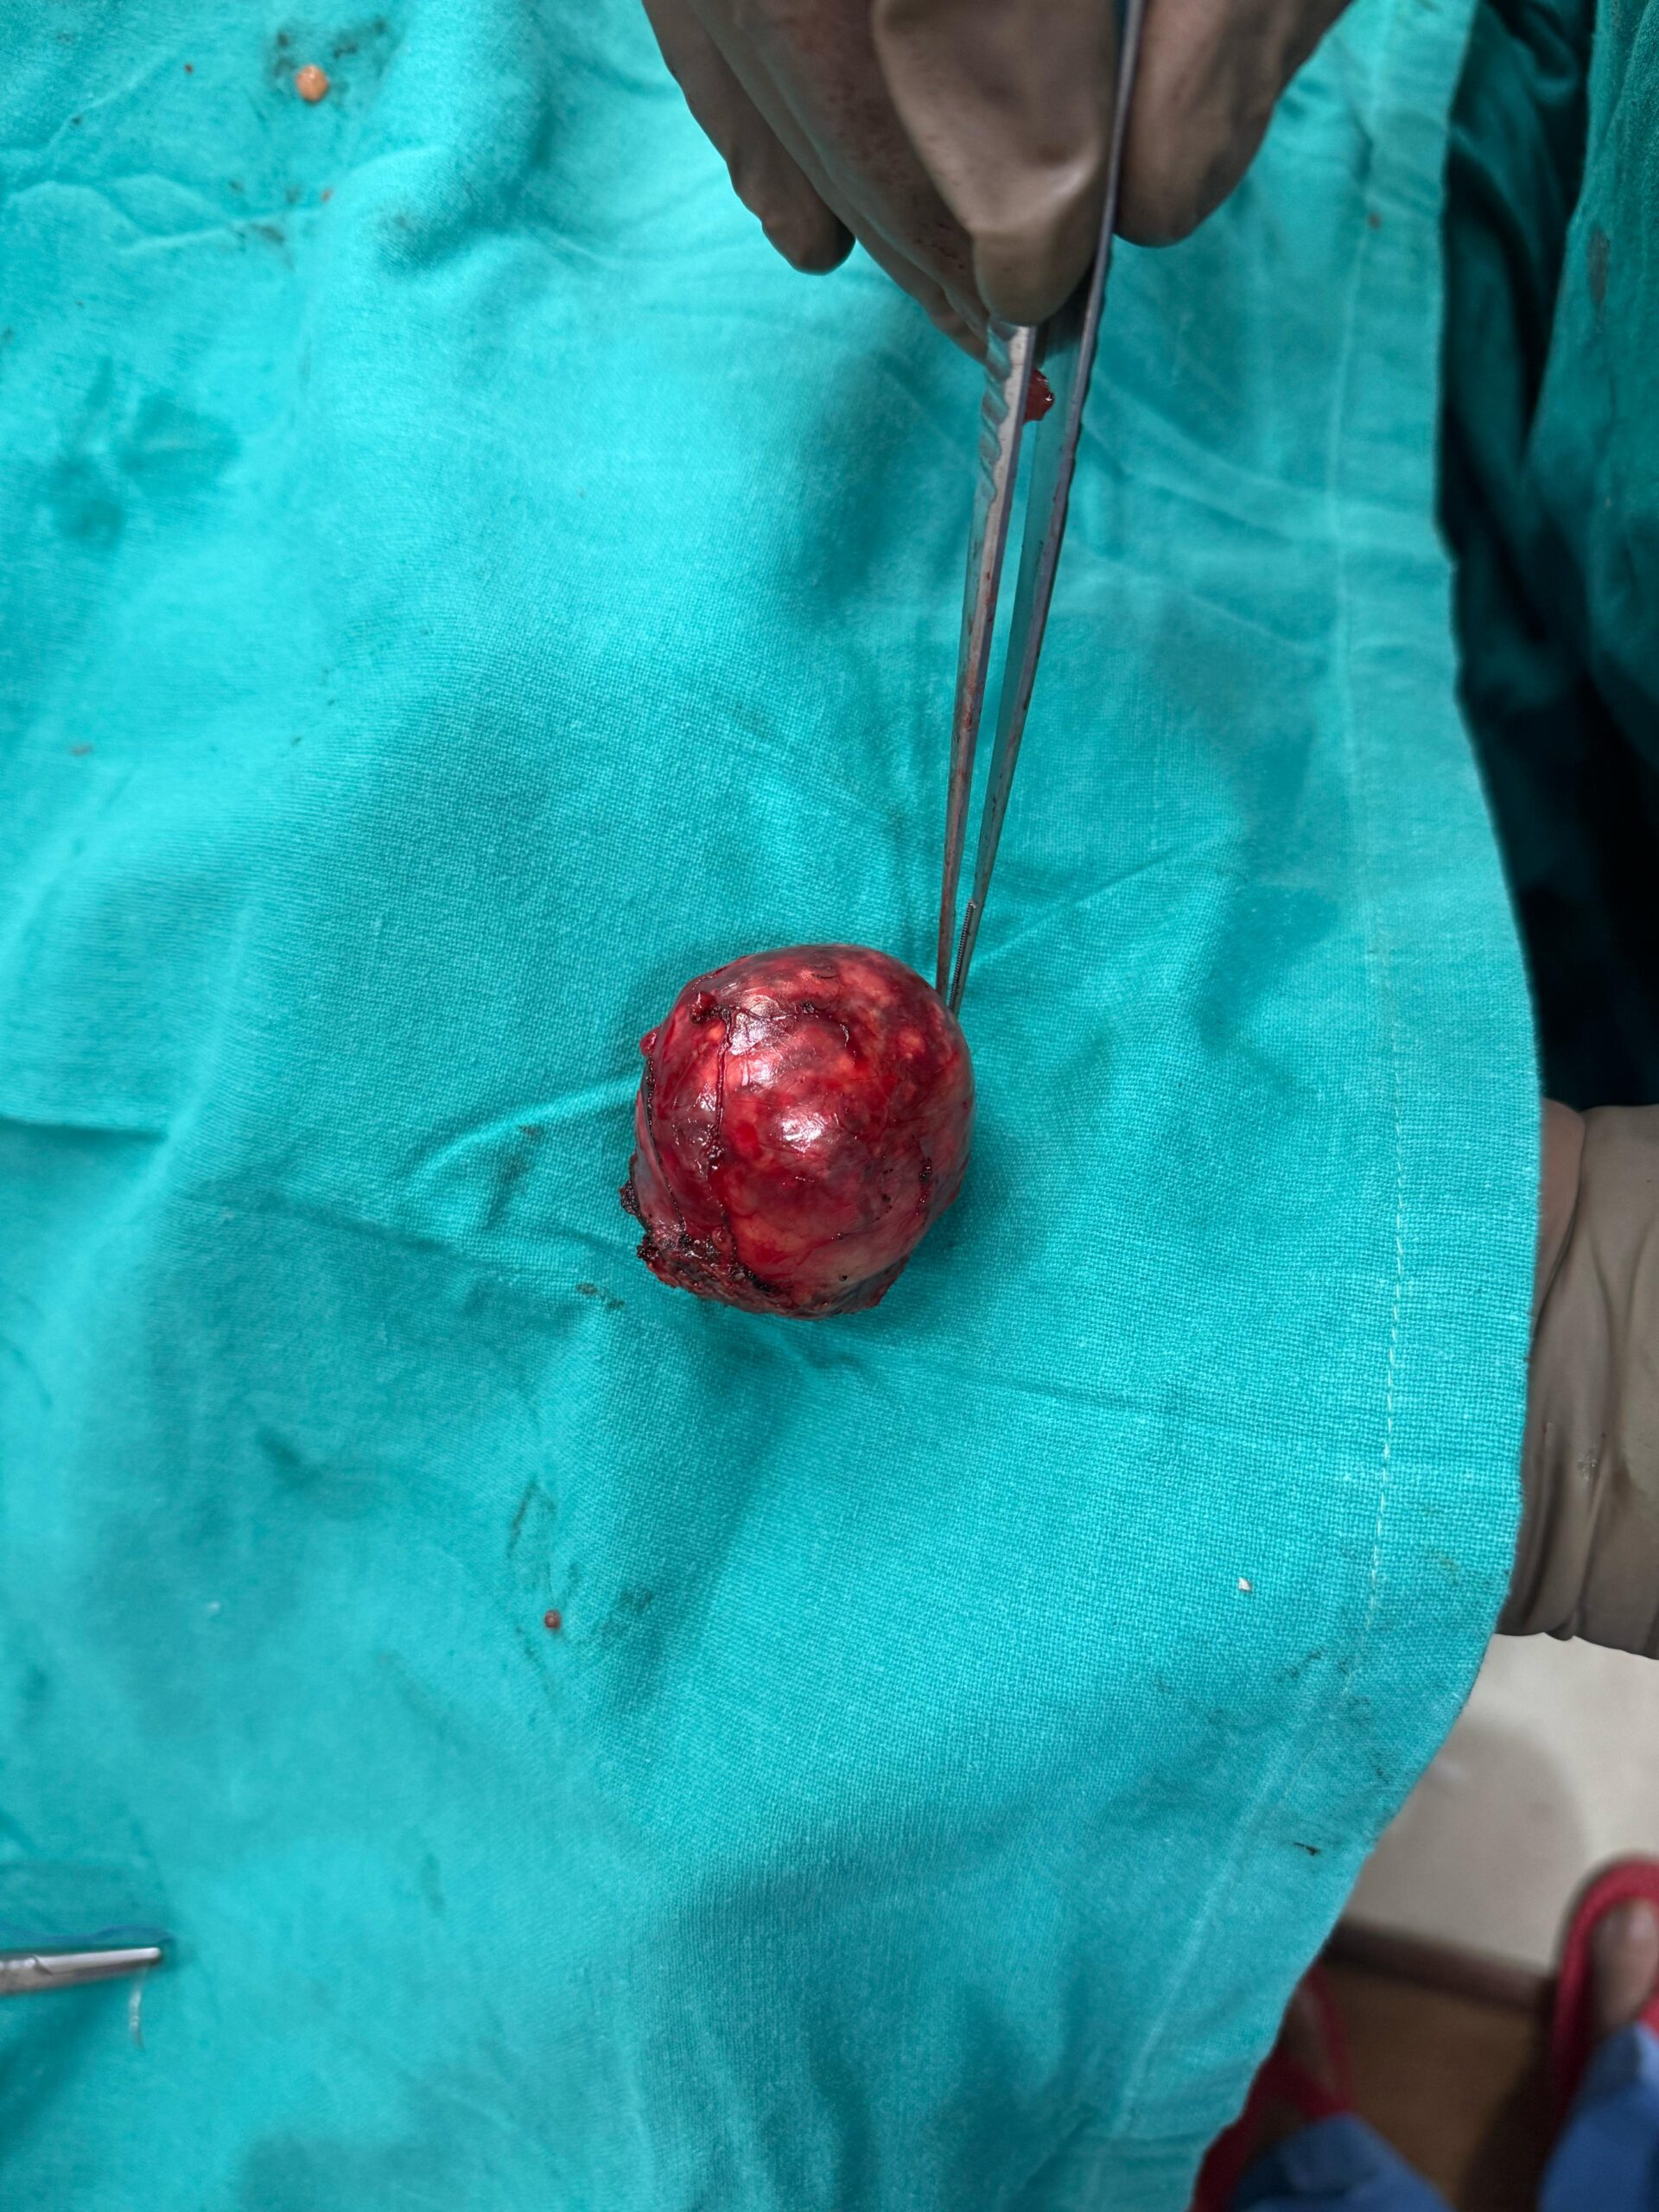

Urological Cancer Treatment

At Jibhakate Urocare Centre in Nagpur, Maharashtra, we specialize in providing comprehensive and advanced urological cancer treatments under the expertise of Dr. Nikhilesh Jibhakate..

Our Gallery